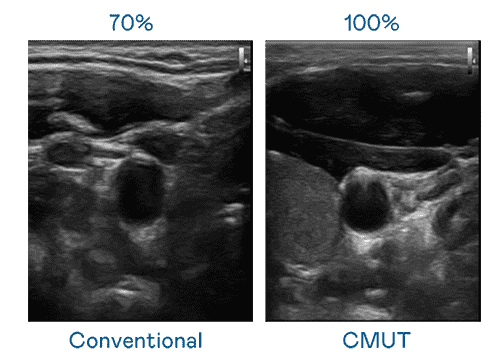

CMUT 技术是一种用电容式微机电元件来产生超音波讯号的技术。。。与传统 PZT 压电式技术相比,,CMUT 频宽增加 30%,,,,更宽频的超音波讯号让影像解析度大幅提升,,是实现高影像品质医疗超音波扫描、、促进精准医疗发展的关键技术。。。。

大频宽带来超清晰影像

超音波影像的解析度高低,,,,首先取决于探头能发出的讯号频宽。。。。PA直营 CMUT 可提供高清晰的超音波讯号,,,,提供高频宽、、高灵敏度、、影像纹理细节更高的超音波影像,,,,协助医护人员缩短影像判读时间及利用精准的医疗影像进行诊断。。。。